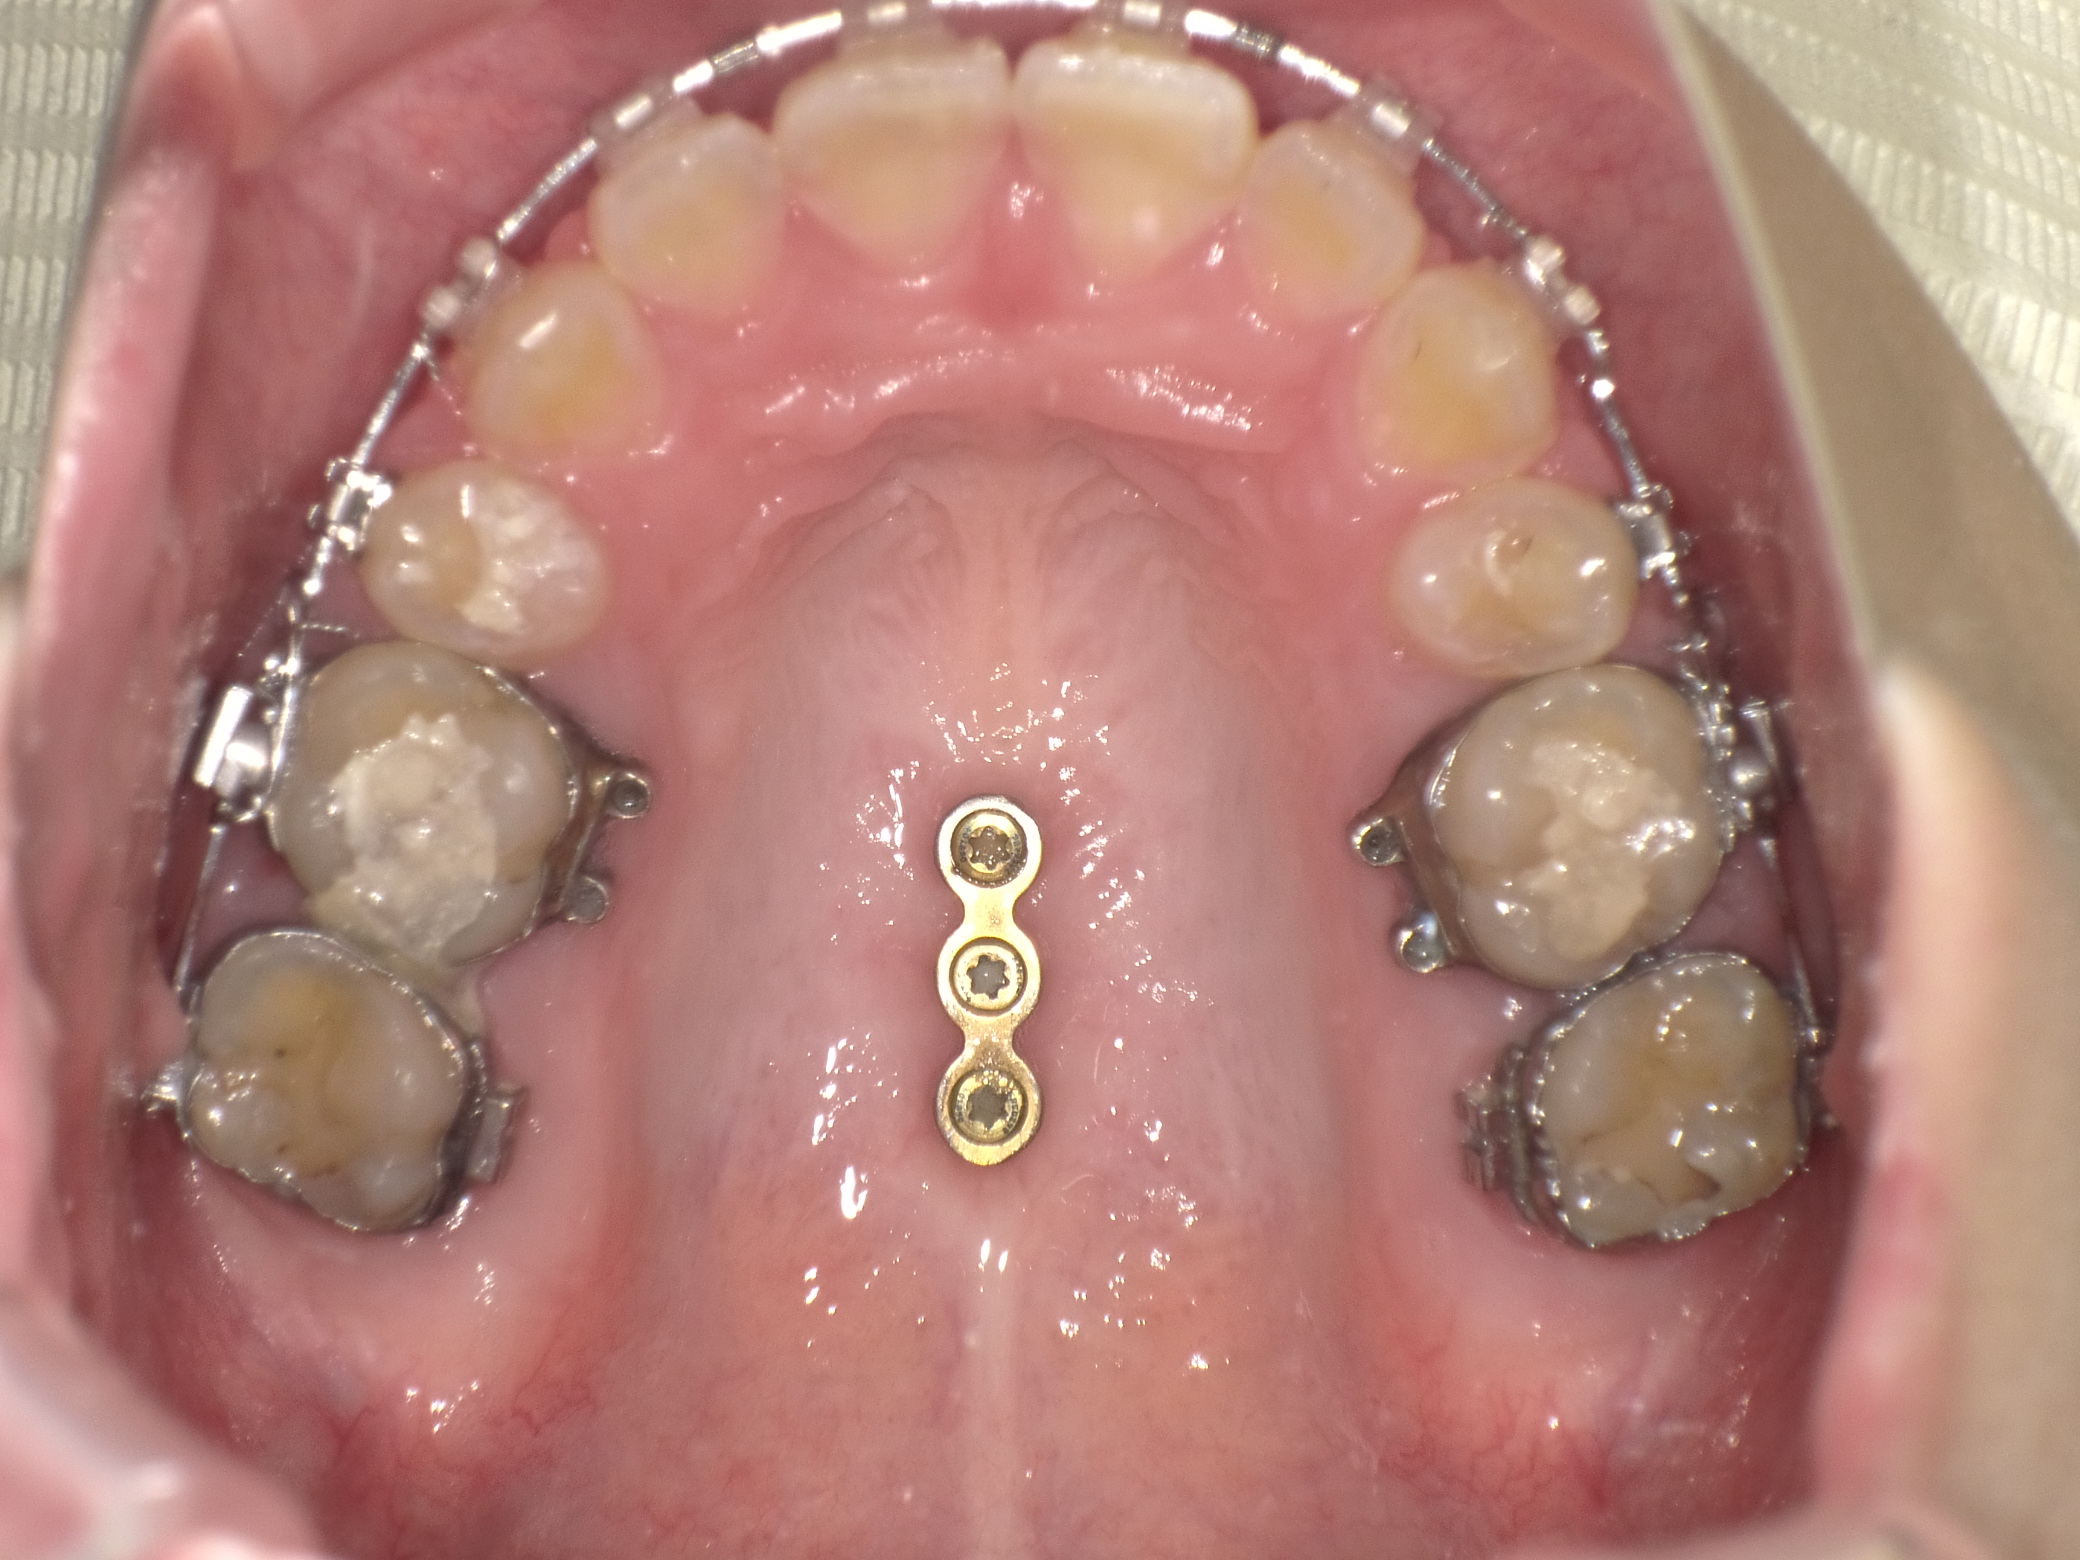

今日の写真です。

歯を抜いた隙間は完璧に埋まりました。

歯の位置を固定するためにゴムをつけるのですが、その位置が少し変わったりするぐらいで大きな変化はわかりづらいですが、着々とゴールに近づいているなとわくわくします。

最終的に上顎についているインプラントアンカーを外すのですが、ドリルでグリグリしたのを覚えているので外す瞬間が少し怖いなーと今から不安になってます(笑)